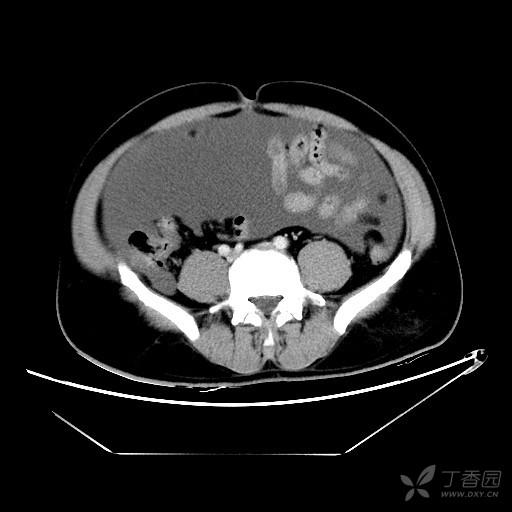

大量腹水,多发囊性占位,猜猜是什么